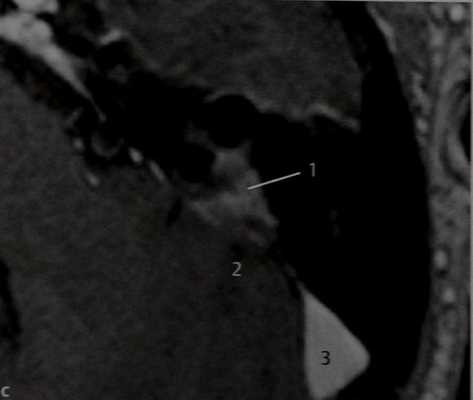

Пациент, обследованный в связи с нейросен-сорной тугоухостью неясной этиологии.

КТ в горизонтальной проекции. В заднем отделе лабиринта вокруг заднего полукружного канала отмечается деминерализация кости. На этом участке кость напоминает «матовое стекло» (1), что характерно для фиброзной дисплазии. Видны также экзофиты (2) во внутреннем слуховом проходе. Гиперостоз и обызвествления в сочетании с симптомом «матового стекла» в области полукружного канала могут быть проявлением менингиомы, хотя твердая мозговая оболочка имеет нормальные очертания.

КТ в вертикальной проекции. Деминерализация кости вокруг полукружного канала (1) не связана с остеофитом (2). Свищей в лабиринте нет. Биопсия подтвердила диагноз фиброзной дисплазии.

МРТ:Т1-взвешенное изображение в горизонтальной проекции после введения препарата гадолиния. Изолированное поражение подтвердилось и на MPT (J), после введения КС сигнал от него несколько усилился. Твердая мозговая оболочка в процесс не вовлечена, интракраниальных очагов обызвествления нет (2). В сигмовидном синусе сохранен кровоток (3).